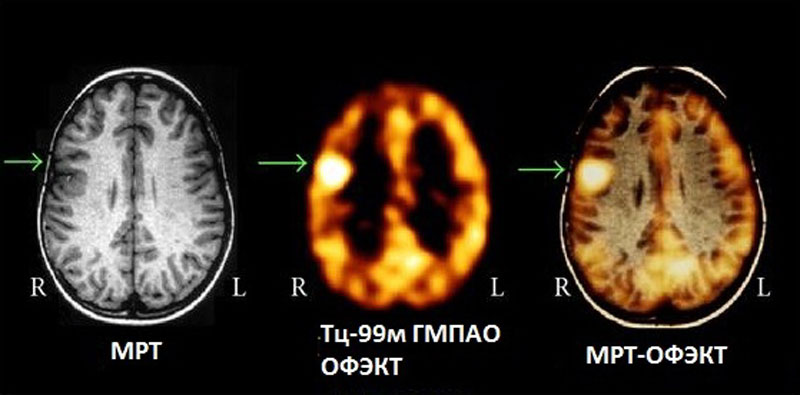

- Современная нейровизуализация (МРТ, ОФЭКТ, SISCOM)

Внедрен современный протокол диагностики эпилептогенных очагов головного мозга — протокол SISCOM (Subtraction Ictal SPECT Co-Registered to MRI)